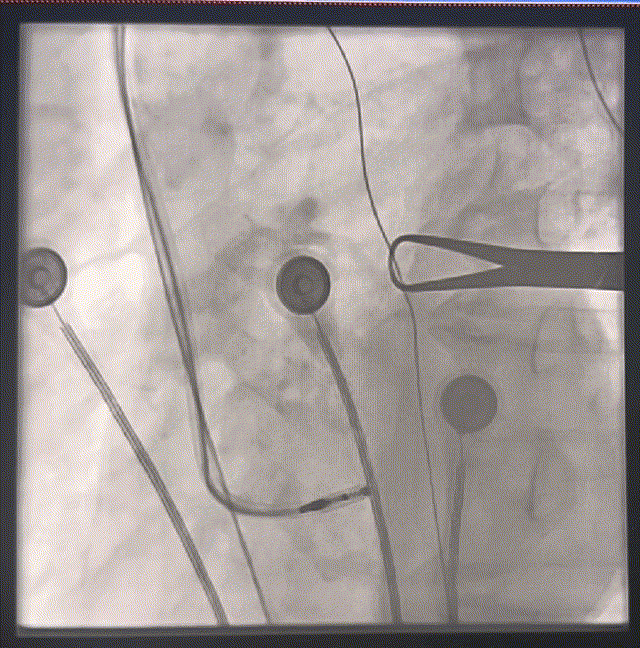

定位左束支

图3

图4